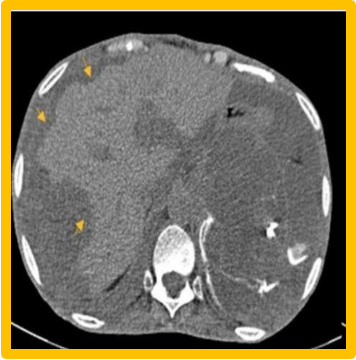

Pseudomyxoma peritonei:

- Rare, commoner in female due to ruptured mucinous cystadenocarcinoma (appendiceal origin in most cases).

- Abdominal distended due to yellow jelly like fluid.

- U/S, CT- scalloped indentation help diagnosis.

- Treatment: Excision of primary, debulking, chemotherapy.

- Recur over months to years